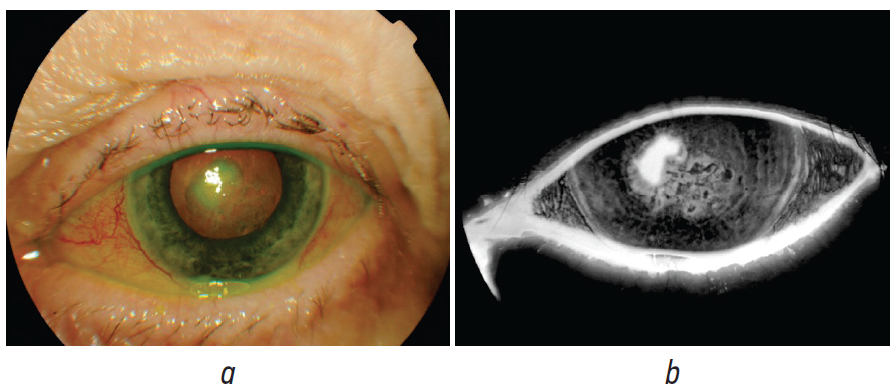

Patient O., 68 years old, was admitted to the emergency room with a grade III alkaline burn of the cornea of the left eye in the late reparative phase (Fig. 2).

Fig. 2. Photo of the anterior segment with fluorescein in patient O.: a — color mode; b — angiography mode of retinal camera

Рис. 2. Фотография переднего отрезка глаза пациентки О. с применением флуоресцеина: a — в цветном режиме; b — в режиме флуоресценции

Upon admission, the visual acuity of the left eye was 0.005, it was not corrected. According to OCT data, the cornea is thickened in the area of the epithelial defect to 599–635 microns, the defect size is 2.58 × 2.67 mm (Fig. 3).

Fig. 3. Optical coherence tomography image of the cornea in patient O. upon hospitalization

Рис. 3. Снимок оптической когерентной томографии роговицы пациентки О. при поступлении